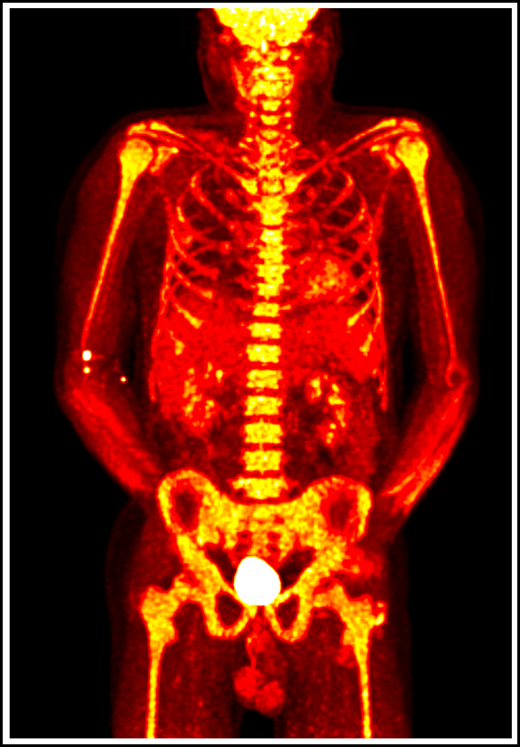

VEXAS is a severe, progressive disease with clinical features that bridge rheumatologic and hematologic conditions. Systemic inflammation involving the skin, lungs, blood vessels, and cartilage often leads to the assignment of various clinical diagnoses, including Sweet syndrome, relapsing polychondritis, polyarteritis nodosa, and giant cell arteritis. Additionally, patients with VEXAS suffer from a spectrum of hematologic problems, including macrocytic anemia, thrombocytopenia, thromboembolic disease, and progressive bone marrow failure, which can evolve to hematologic malignancy (Figure 1). An increased risk for hematologic malignancy, most notably myelodysplastic syndrome (MDS), has been reported in many rheumatologic diseases, and conversely, MDS has been associated with a variety of autoimmune syndromes.4-8 VEXAS syndrome may explain some of these historic clinical associations.

18F-fluorodeoxyglucose positron emission tomography in a patient with VEXAS syndrome demonstrating hypermetabolic activity in bone marrow (yellow). Somatic mutations in UBA1 in hematopoietic cells lead to myeloid-driven inflammation that is often refractory to treatment in patients with VEXAS syndrome.